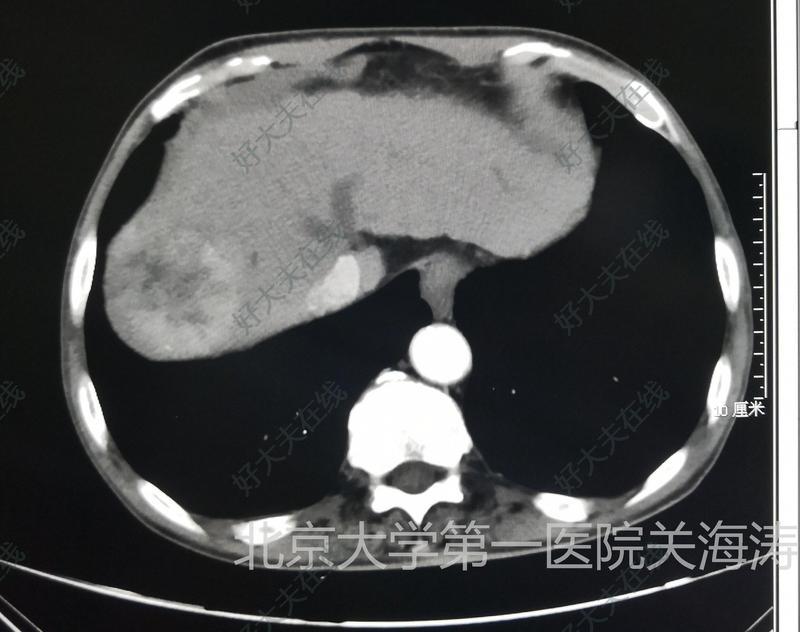

經(jīng)常有患者咨詢介入醫(yī)生是如何治療小肝癌的?下面分享一個小肝癌介入治療的過程供大家參考。右肝小肝癌,見紅色箭頭。其上方低密度灶為肝囊腫。先行介入造影及碘油栓塞減少腫瘤血供并標(biāo)志腫瘤位置。介入栓塞后病灶可見碘油沉積。CT引導(dǎo)下用微波消融針穿刺病灶并進(jìn)行消融治療。拔針后可見消融范圍呈低密度完全覆蓋腫瘤,提示腫瘤被完全消融。點評:小肝癌以往一般采取外科手術(shù)治療,隨著消融技術(shù)的不斷進(jìn)步,目前消融治療也是肝癌治療的首選方案,特別適用于難于耐受外科手術(shù)的患者。消融治療微創(chuàng)價格相對便宜,恢復(fù)快,未來會被更多患者選擇。